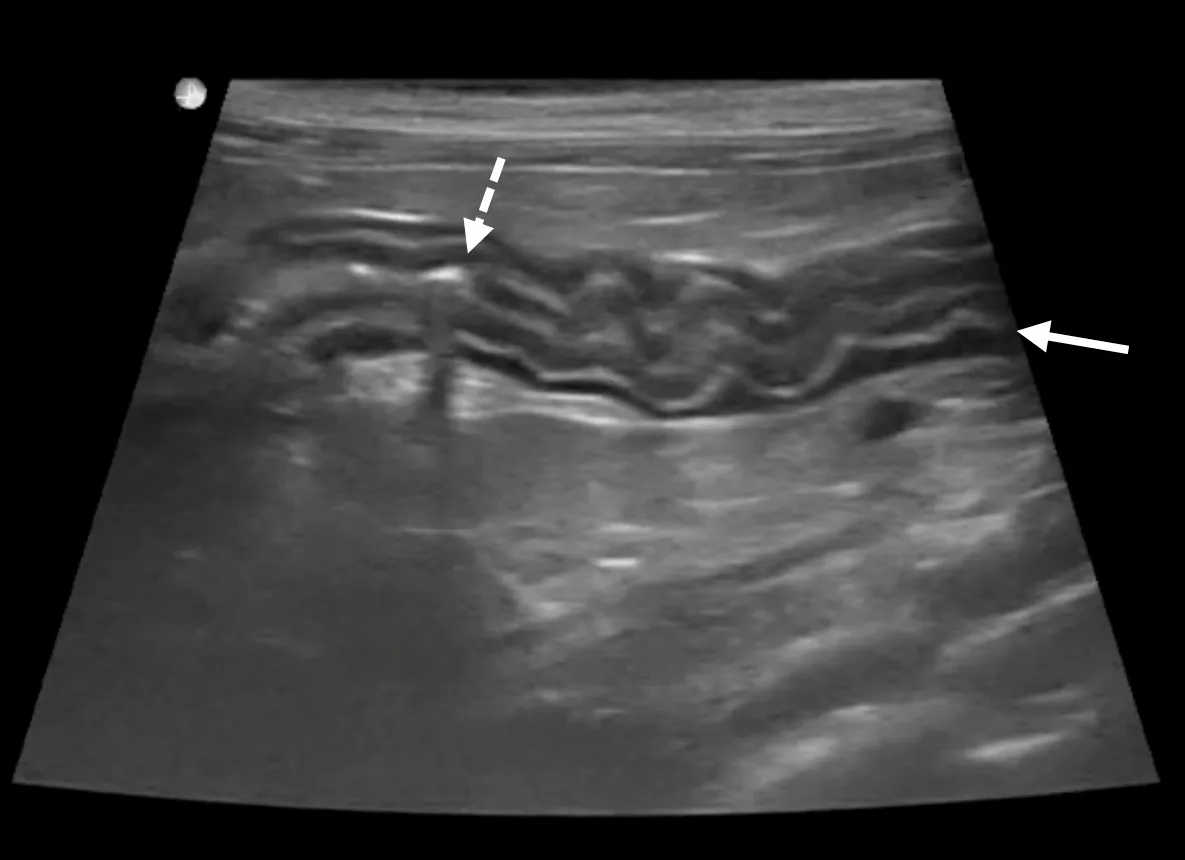

Intestinal biopsies are required for definitive diagnosis, to rule out differentials (eg, neoplasia, certain infectious diseases), and to allow further classification of IBD based on cellular infiltration type (eg, eosinophilic, neutrophilic, lymphocytic/plasmacytic).21 Most feline IBD is caused by lymphocytic/plasmacytic and/or eosinophilic inflammation.21 Combining GI biopsies with immunohistochemistry and PCR for antigen receptor rearrangement (ie, PARR) improves the ability to differentiate IBD from lymphoma.3 Biopsies should be obtained through an endoscopic or full-thickness surgical approach (Figure 2). Applying and interpreting clonality testing presents additional clinical challenges; discussion is available in the literature.2-4

Classic belly button appearance of the ileocolic junction during routine colonoscopy. The shiny mucosal lining appears slightly hyperemic and edematous, although these findings can occur secondary to the endoscopy procedure. Partially open entry to the blind sac of the cecum is visible (arrow).